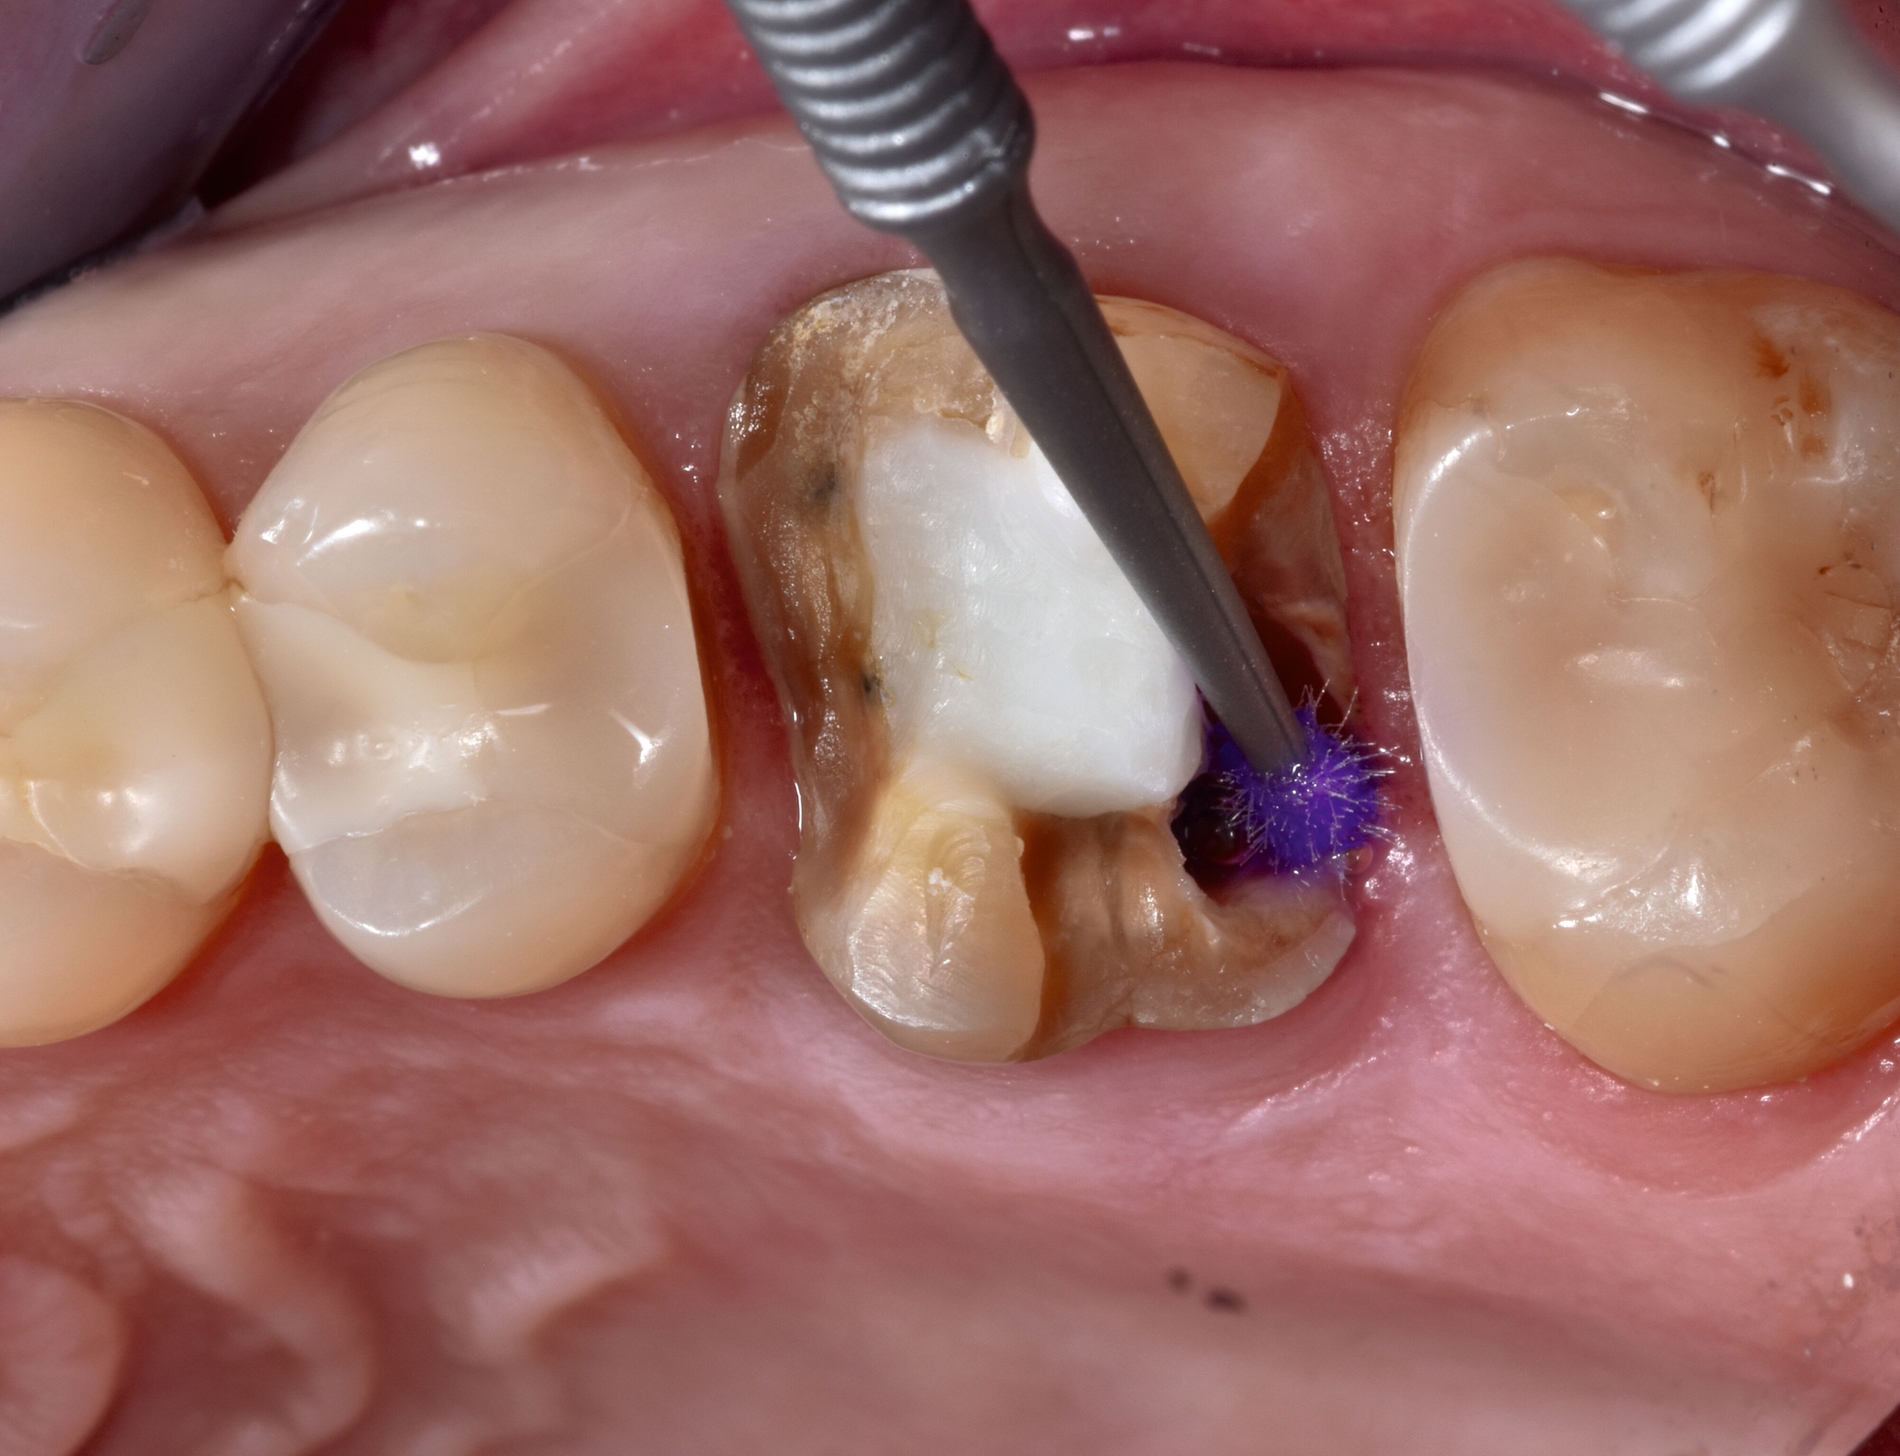

Je nach Befestigungsmaterial kann vor der Lichtpolymerisation ein Glycerin-Gel auf den Zementspalt aufgetragen werden. Nach Lichthärtung von allen Seiten werden die Überschüsse entfernt, die Okklusion wird eingeschliffen und die Restauration abschließend poliert. Es finden zudem eine Anpassung von Interdentalraumbürsten sowie eine Mundhygieneinstruktion statt. Darüber hinaus wird die Patientin über notwendige regelmäßige Kontrollen im Sinne der präventiven Erhaltungstherapie aufgeklärt.

Bei der Kontrolle nach sechs Monaten zeigen sich an Zahn 26 entzündungsfreie Verhältnisse und kein Anhalt auf Lockerung oder erhöhte Sondierungstiefen. Die Patientin verwendet täglich eine Interdentalraumbürste als Hilfsmittel zur häuslichen Mundhygiene. Zur Kontrolle wird ein Zahnfilm angefertigt. Röntgenografisch zeigt sich im distalen Bereich des Zahnes 26 die Kastenelevation aus Komposit mit stufenlosem Übergang zur indirekten keramischen Deckrestauration (Abbildung 4).